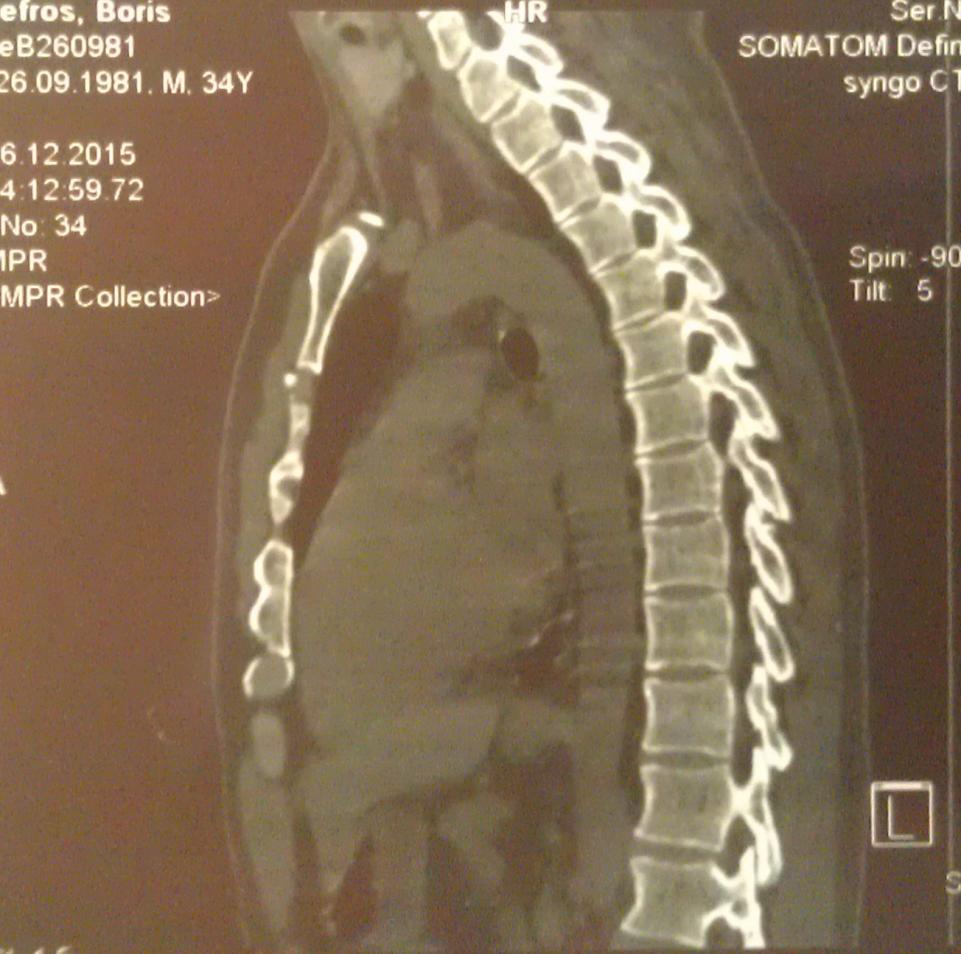

А достаточно ли плохих ревмопроб и компьютерной томограммы, где виден кифоз - чтобы поставить диагноз "болезнь Бехтерева"?

Вот моя компьютерная томограмма позвоночника.

Вложение 1182Вложение 1184Вложение 1185Вложение 1186Вложение 1183